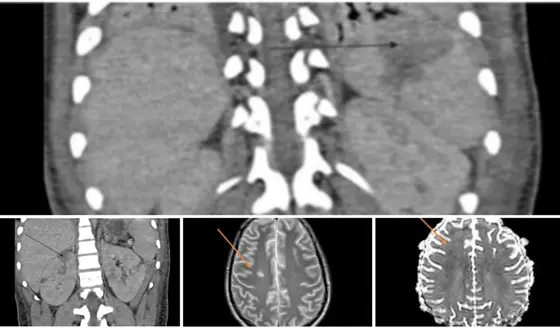

Síndrome inflamatorio multisistémico pos-COVID-19 en adolescente con miocardiopatía y lesión renal